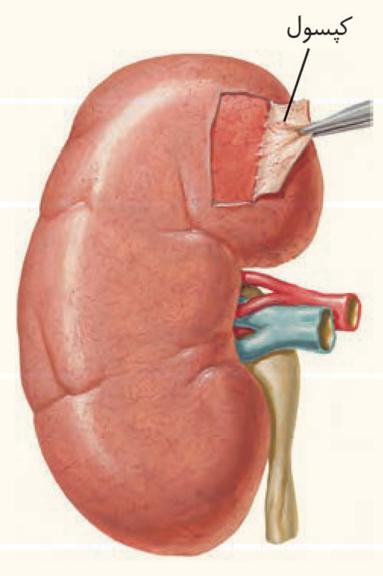

دندهها ازبخشی از کلیه محافظت میکنند. علاوه بر این، پردهای از جنس بافت پیوندی به نام کپسول کلیه، هر کلیه را در بر گرفته است.

چربی اطراف کلیه، علاوه بر اینکه کلیه را از ضربه محافظت میکند در حفظ موقعیت کلیه نقش مهمی دارد. تحلیل بیش از حد این چربی در افرادی که برنامه کاهش وزن سریع و شدید به کار میگیرند ممکن است سبب افتادگی کلیه و تاخوردگی میزنای شود. در اینصورت، فرد با خطر بسته شدن میزنای و عدم تخلیه مناسب ادرار از کلیه روبهرو میشود که در نهایت به نارسایی کلیه خواهد انجامید.

الف) عاملی که با بریدن قسمتی از آن به راحتی جدا میشود، با ساختار خارج کننده از ادرار از کلیه در تماس است.

عوامل حفاظتکننده از کلیه کپسول کلیه، چربی اطراف آن و دندهها هستند.

الف) درست. عاملی که با بریدن قسمتی از آن به راحتی جدا میشود کپسول کلیه است. کپسول کلیه با میزنای(ساختار خارجکننده ادرار از کلیه) در تماس است.

کپسول کلیه با بریدن قسمتی از آن به راحتی جدا میشود و میتواند در قسمت هایی با میزنای که در خارج کردن ادرار از کلیه نقش دارد در تماس باشد.